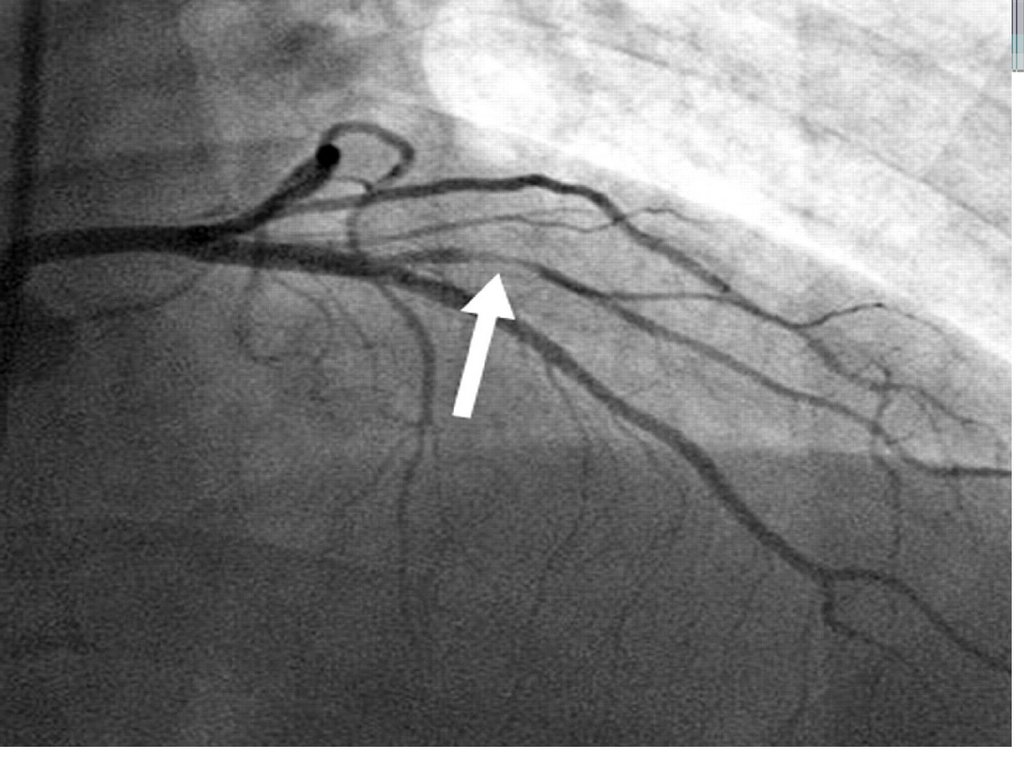

ОКС без подъема сегмента ST

Неокклюзирующий(зачастую реканализированный тромб в просвете крупной

коронарной артерии;

Окклюзия коронарной артерии мелкого калибра (1-2 мм диаметра);

Неокклюзирующий

тромб

16.

17.

18.

19.